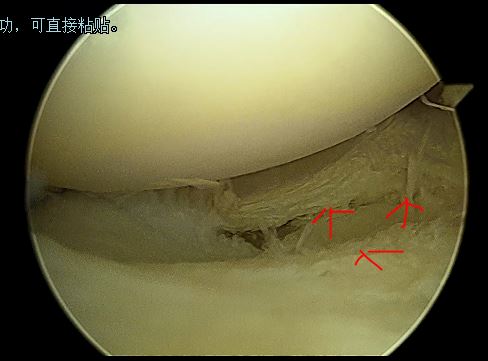

半月板内部分层撕裂

中央部撕裂

盘状半月板进行修整成形及缝合后

(外侧盘状半月板并撕裂,修整缝合后恢复正常的半月板形态)

(因此我们微创的关节镜技术可以修复损伤的盘状半月板)